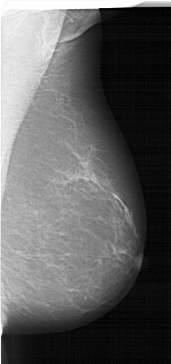

A_1541_1.RIGHT_CC

RIGHT_CC LINES 6016 PIXELS_PER_LINE 3286 BITS_PER_PIXEL 12 RESOLUTION 43.5 NON_OVERLAY